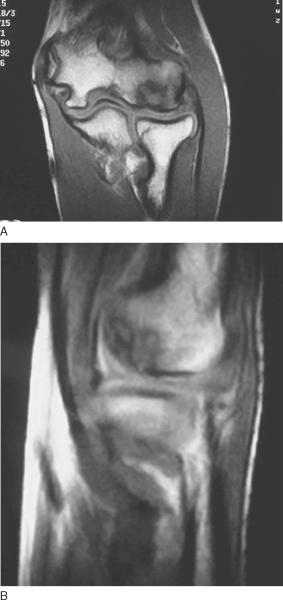

Magnetic resonance imaging has become the standard modality for further evaluation. [4] [28] Not only can magnetic resonance imaging assess the articular surface, but it can also define both size and extent of the lesion (

Fig. 32-2

). Early, stable lesions show changes on T1-weighted images, but T2-weighted images remain normal. On the other hand, advanced lesions show changes on both T1- and T2-weighted images. [4] [8] Loose in situ lesions have a cyst under the lesion. Magnetic resonance arthrography can improve the diagnosis with leakage of dye beneath the disrupted cartilage. [8] [28]

Figure 32-2 . Increased signal of the T2 image indicates disruption of the articular surface. |